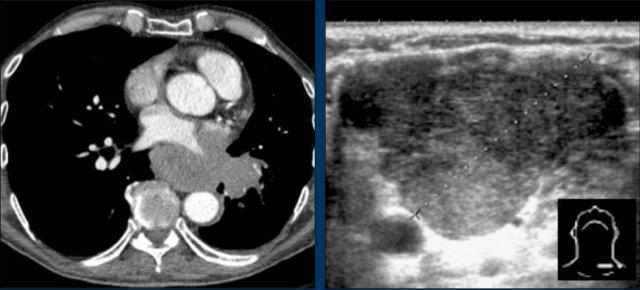

Ca Lâm Sàng 1: Tràn Dịch Màng Ngoài Tim Giả Tim To

- Trên phim X-quang ngực, bệnh nhân có vẻ như bị giãn tim.

- Tuy nhiên, hình ảnh CT cho thấy rõ ràng rằng sự to ra bề ngoài này là do tích tụ dịch màng ngoài tim đáng kể, chứ không phải do giãn buồng cơ tim thực sự.

Chảy Máu Màng Ngoài Tim Sau Phẫu Thuật

Ở bệnh nhân vừa trải qua phẫu thuật tim, sự thay đổi đột ngột kích thước tim trên X-quang ngực cần gợi lên nghi ngờ chảy máu màng ngoài tim, một biến chứng có thể đe dọa tính mạng.

Ca Lâm Sàng 2:

- Một bệnh nhân sau phẫu thuật có sự thay đổi bóng tim.

- Siêu âm tim chỉ phát hiện tràn dịch màng ngoài tim tối thiểu.

Ca Lâm Sàng 2 – Hình ảnh CT

- CT cho thấy tràn dịch màng ngoài tim sau lượng lớn đang chèn ép thất trái (mũi tên xanh dương: dịch tràn; mũi tên đỏ: thất trái bị chèn ép, có ngấm thuốc cản quang).

- Phẫu thuật thám sát xác nhận khối máu tụ màng ngoài tim sau lớn.

Lưu ý: Lượng dịch tối thiểu ở phía trước trên siêu âm có thể đánh giá thấp thể tích thực sự nếu dịch tràn khu trú ở phía sau, nhấn mạnh giá trị của CT trong các trường hợp sau phẫu thuật.

Đặc biệt ở những bệnh nhân vừa trải qua phẫu thuật tim, sự to ra của bóng tim có thể là dấu hiệu của chảy máu màng ngoài tim.

Bệnh nhân này có sự thay đổi hình dạng tim (tầm quan trọng của hình ảnh trước đó) và chảy máu màng ngoài tim được nghi ngờ.

Siêu âm chỉ phát hiện tràn dịch màng ngoài tim tối thiểu.